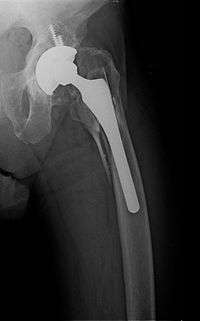

- Periprosthetic fracture – A fracture at the point of mechanical weakness at the end of an implant